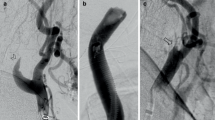

We classified the cases into two groups by the delineation of vessels with preoperative MR angiography as follows: Group G, good-escape-route group with AcoA and bilateral A1 with/without ipsilateral PcoA; and Group P, poor-escape-route group which did not fulfill the criteria of Group G. Patterns of escape routes observed in this series are shown in Fig. 2.

Variation in collateral pathways as escape routes observed in the enrolled cases. Dotted lines indicate estimated evacuation routes of increased blood flow from the reconstructed internal carotid artery (ICA). G1-4 belong to good-escape-route group (Group G) and P1-9 belong to the poor-escape-route group (Group P)

Hyperemia and CHS

There were two patients that showed hyperemia, one undergoing CAS (Case 58, Table 1) and the other CEA (Case 60). Both patients belonged to Group P (bilateral A1 but without AcoA, P9 in Fig. 2) and were Type I. Although the mean rCBF increase rates of the operative sides were 83.8 and 82.8 %, respectively, neither patient showed any neurological symptoms due to hyperemia.

There were two CAS patients showing CHS during the investigated period. As their poor conditions prevented SPECT 2 days after the operation, which was mandatory to fulfill the criteria of the enrollment, both patients were excluded from further analysis (Fig. 1). The first case was a 74-yearold man with atrial fibrillation controlled with warfarin underwent CAS for 83 % asymptomatic stenosis of right carotid. Preoperative evaluation revealed right A1 without AcoA and left A1 on MR angiography, placing him in this study’s Group P. There were no apparent low rCBF areas on the preoperative SPECT at rest. A postoperative CT disclosed massive intracranial hemorrhage (ICH) on the right hemisphere after successful stent placement. The other case was an 80-year-old woman with 95 % stenosis of the right carotid. Preoperative MR angiography demonstrated right A1 and AcoA without left A1, again corresponding to Group P. A mild decrease in the right hemisphere (85 % of the normal value) was observed on preoperative SPECT at rest. She showed hypovolemic shock due to bleeding for anticoagulation after successful stent placement but recovered without neurological deficit. On the sixth postoperative day, she showed sudden general convulsion and deterioration of consciousness with no evidence of new infarction, presumed to be ascribable to hyperperfusion or reperfusion syndrome [10]. Postoperative SPECT after one month revealed a relative rCBF increase on the operative side, corresponding to Type I in the present study (data not shown).

Involvement of PcoA

The patency of a collateral artery such as AcoA and of bilateral A1 arteries has been thought to relate to hyperperfusion after CEA/CAS because blood flow supplied from these vessels affects the rCBF and vascular reserve of the ACA and MCA areas [20]. In the present study, the importance of AcoA and A1 as escape routes was emphasized when the focus was excessive postoperative blood flow into the ICA-supplying area of the operative side.

The relevance of PcoA to collateral flow has been described previously [17], but no remarkable effect was observed in postoperative rCBF increase rates in either Groups G or P, whether ipsilateral PcoA was delineated or not, and bilateral PcoA was not a significant factor for unilateral rCBF increase on multivariate analysis. Thus the PcoA does not seem to be important at least as a postoperative escape route, in contrast to ipsilateral A1 and AcoA. Prediction of CHS by preoperative degree of MCA delineation by single slab 3.0-T MR angiography was proposed recently [11]. Cases with good delineation of MCA branches on the stenosis side appeared at low risk of decreased CVR, and hence CHS. With this method, cases with bilateral A1 but without AcoA so that blood flow to the ACA and MCA is supplied by each side of the ICA are considered to be at low risk of hyperperfusion due to sufficient preoperative blood flow and good CVR. In our present study, however, those cases seemed to be at high risk for hyperperfusion when escape routes were poor, concentrating cerebral blood flow on the operative hemisphere.